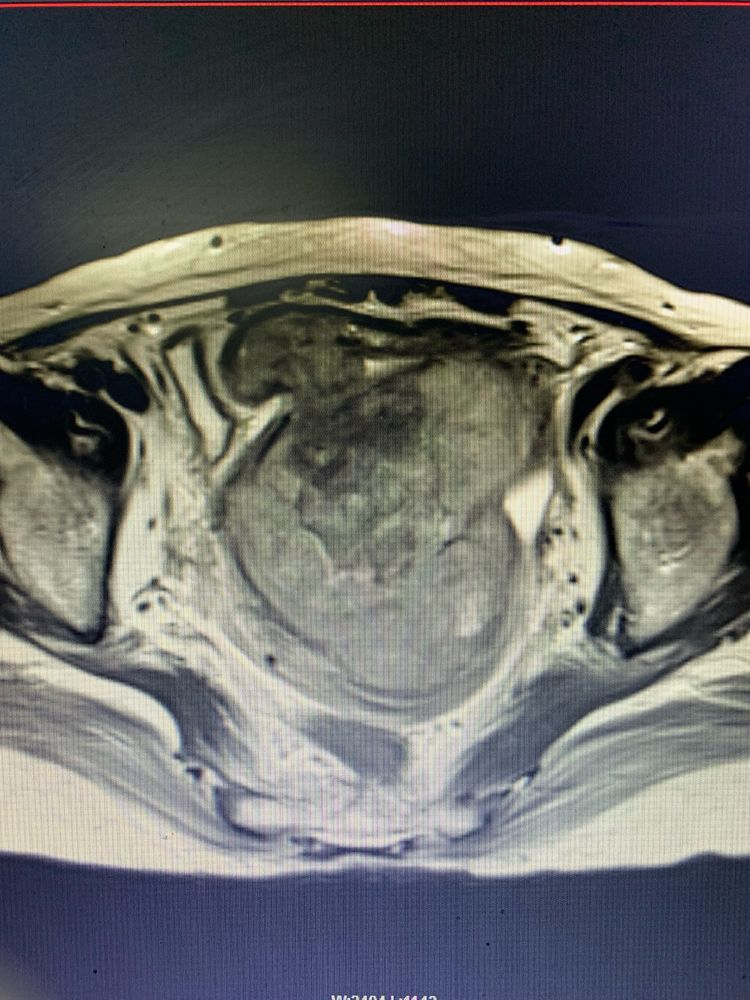

董徐男主任熱情接待并立即安排患者入院完善進(jìn)一步檢查。行VCT及MR檢查提示:盆腔巨大占位病變,考慮子宮或左附件來源的惡性腫瘤,腫塊前方侵犯乙狀結腸全層,患者手術指征明顯,由于手術範圍大、風險高,董徐男主任積極申請醫院多學(xué)科會(huì)診,通過(guò)邀請胃腸肝膽外科、病理科、放射科、功能(néng)科、消化内科、麻醉手術中心、眼科、腫瘤血液科、心血管内科/老年病科、營養科、泌尿外科、重症醫學(xué)科等多學(xué)科進(jìn)行會(huì)診,評估患者病情,做好(hǎo)術前準備。

入院初步考慮是子宮腫瘤,放射科吳慧忠主任、鄭業坤副主任醫師結合患者影像學(xué)情況,組織全科讨論研究,認爲可能(néng)是子宮意外來源的腫瘤侵入子宮内生長(cháng),并考慮有腸道(dào)轉移可能(néng);